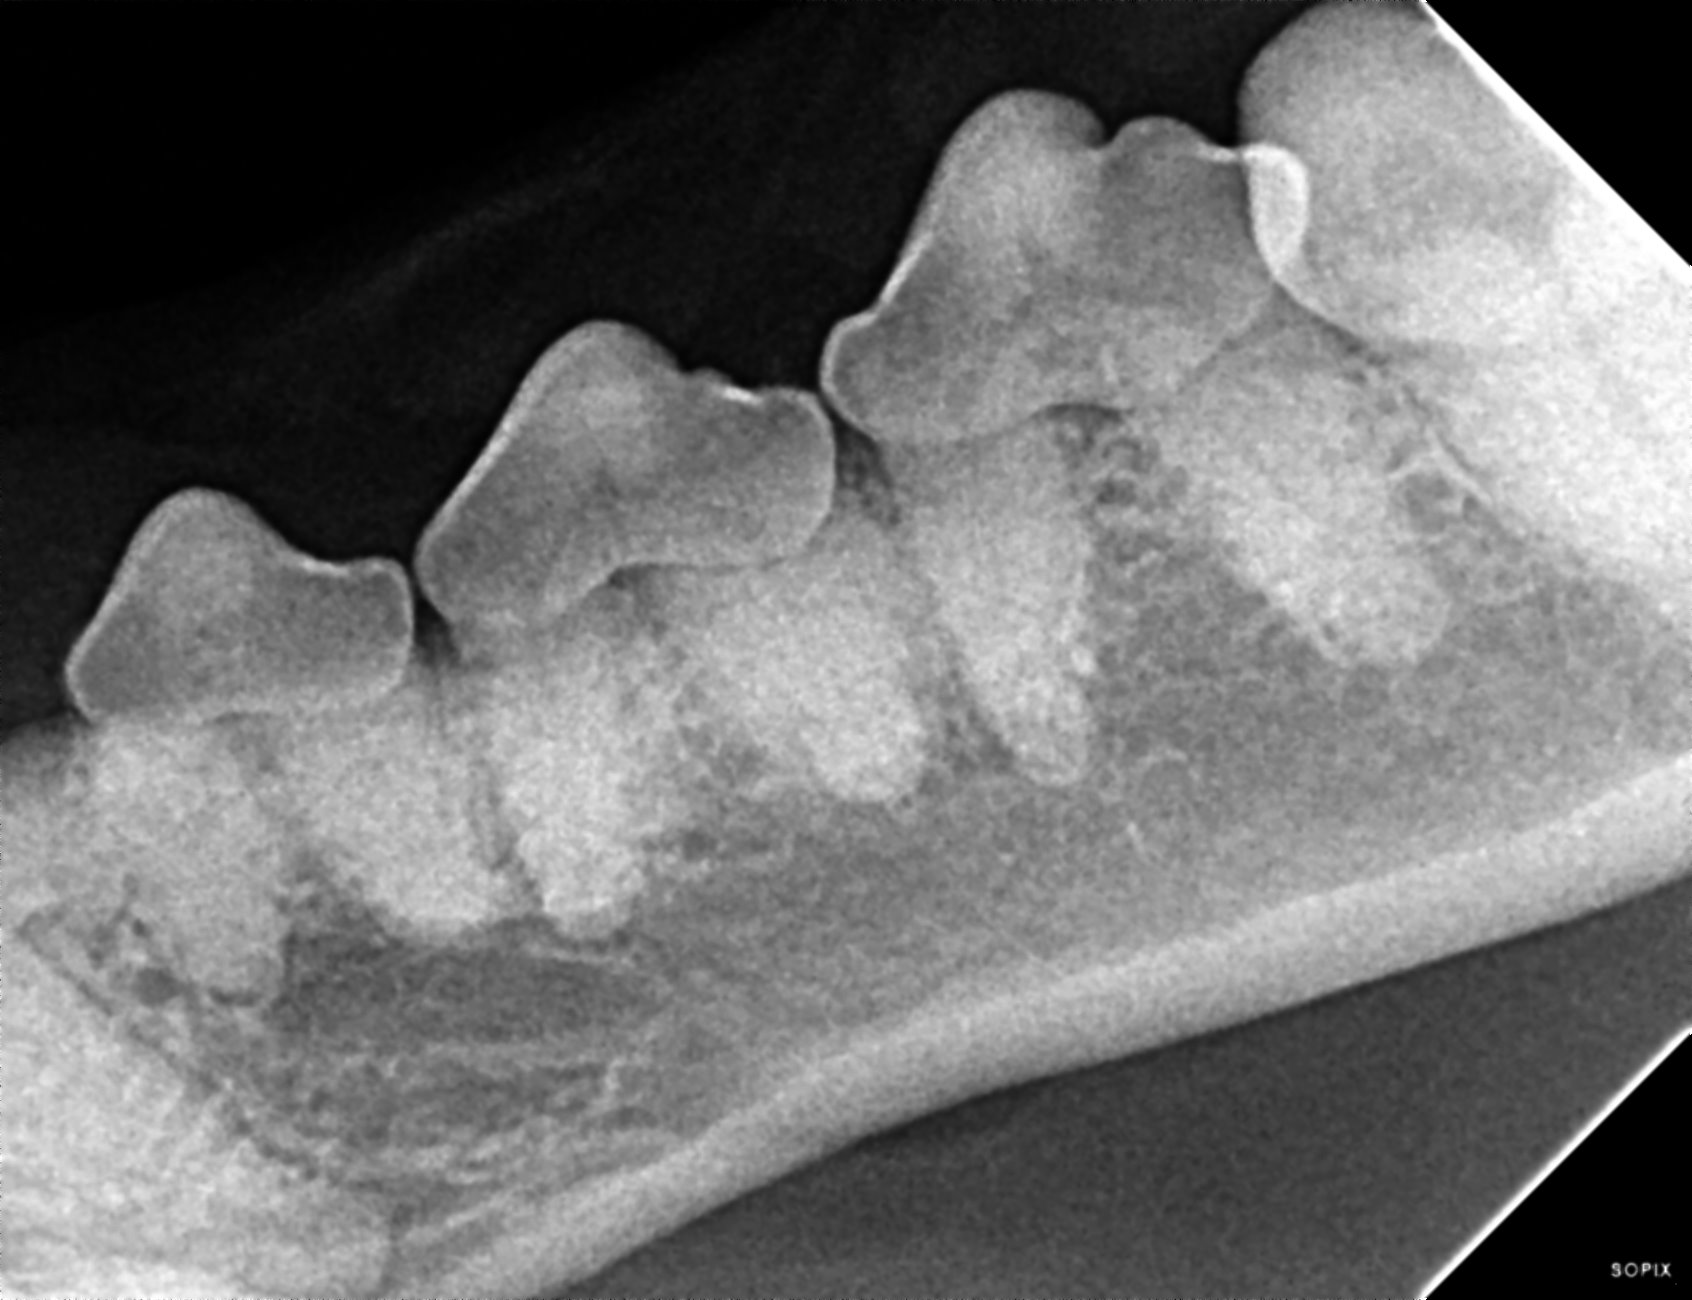

The prophylactic dental includes x-rays of all the teeth, ultrasonic scaling of the plaque and tartar from the teeth, polishing, and fluoride treatment. It is impossible to determine the full extent of dentistry your pet needs until they are under anesthesia and we can examine each tooth individually, but we can give an estimate of your pets dental status and needs during your routine exam.

We all love kisses from our fur babies, but sometimes the odor can be too much. The odor is a result of bacteria and plaque that accumulate on our pet’s teeth and lead to inflamed gums, periodontal infections, and in severe cases, abscessed teeth. We prefer to be proactive and perform routine cleanings every 1-2 years. When dental disease goes unnoticed and untreated, it can lead to bacteremia or bacteria entering the bloodstream. Once this occurs, it can cause irreversible damage to internal organs like the heart and kidney or can seed infection in the joints and spine. We don’t often think about it, but our dentist recommends we brush our teeth two or three times a day, then have a prophylactic dental cleaning every 6 months to prevent the conditions we just mentioned.